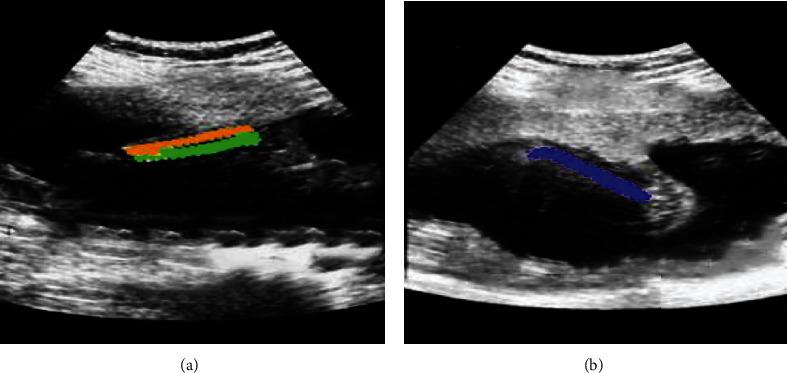

This research was aimed at analyzing the role of ultrasound-guided nerve block based on intelligent three-dimensional (3D) reconstruction algorithm in intraoperative anesthesia and postoperative analgesia of orthopedic surgery. 68 elderly patients were undergoing orthopedic surgery on the lower extremities, and they were randomly rolled into two groups with 34 patients in each group. The patients in control group received sciatic nerve block anesthesia (SNBA), and the patients in the experimental group received ultrasound-guided SNBA (UG-SNBA) under 3D reconstruction algorithm to analyze and compare the anesthesia effect and the postoperative analgesia effect. The results showed that compared with other algorithms, the evaluation index of ultrasound images processed by the 3D reconstruction algorithm was better. In terms of anesthesia effect, there was no significant difference in systolic blood pressure, diastolic blood pressure, and heart rate between the two groups before surgery ( > 0.05). Intraoperative and postoperative indicators of the experimental group were significantly better than those of the control group; the drug dosage (61 mg) was less than that of the control group (78 mg). In addition, the onset time of anesthesia, the time of pain blockade, and the postoperative awake time (5 minutes, 8 minutes, and 8 minutes, respectively) were shorter than those in the control group (13 minutes, 15 minutes, and 15 minutes, respectively). The visual analogue scale (VAS) scores of the experimental group were better than those of the control group on the day after surgery, one day after surgery, two days after surgery, and three days after surgery, with significant differences ( < 0.05). In summary, 3D reconstruction algorithm-based ultrasound image effect was clearer, the effect of UG-SNBA was more stable, and the postoperative analgesic effect was better. This work provided a higher reference for the selection of safe and effective anesthesia options in orthopedic surgery.